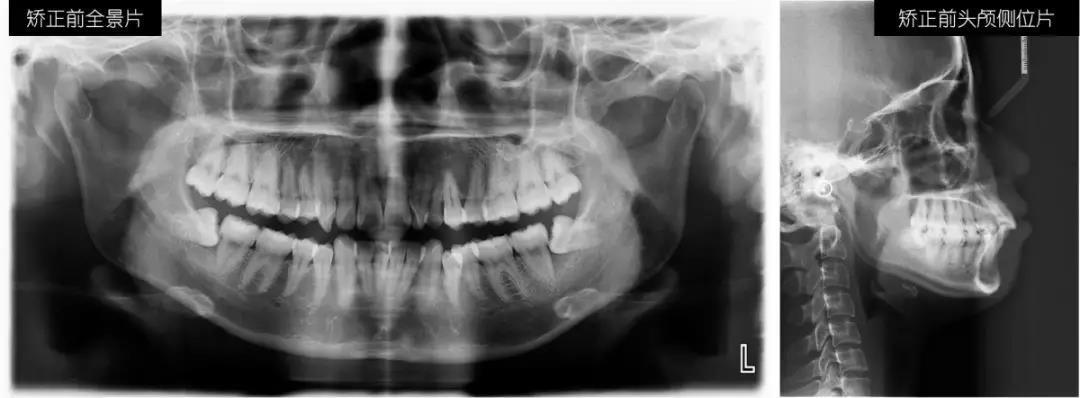

戴时代天使牙套前,我分了两次拔了下排左右2颗多余的智齿,还确认了时代天使3D动画设计方案,直观地看到,在即将到来的日子里,我的牙齿是如何通过片切留出移动排齐的空间,如何一步步移动到理想状态。